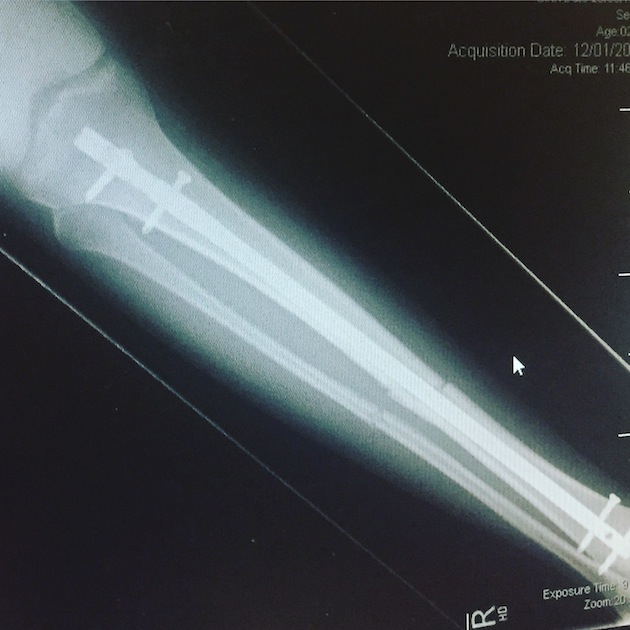

“I was in hospital for five days, I had a rod through my knee and ankle, and was only allowed to bear weight on the balls of my feet for seven weeks.